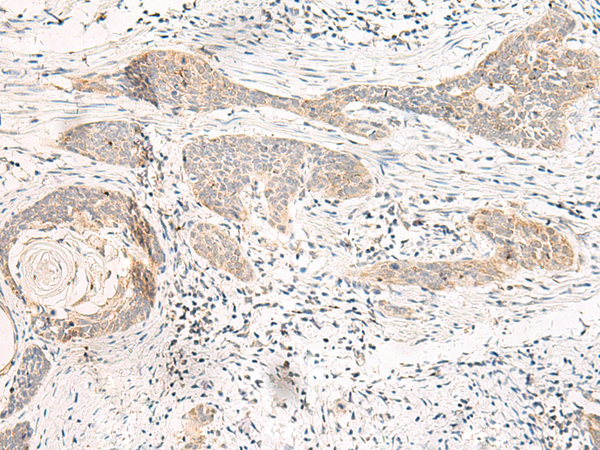

分类: 科研抗体货号: P13565别名: EULIR应用: IHC反应种属: Human, Mouse